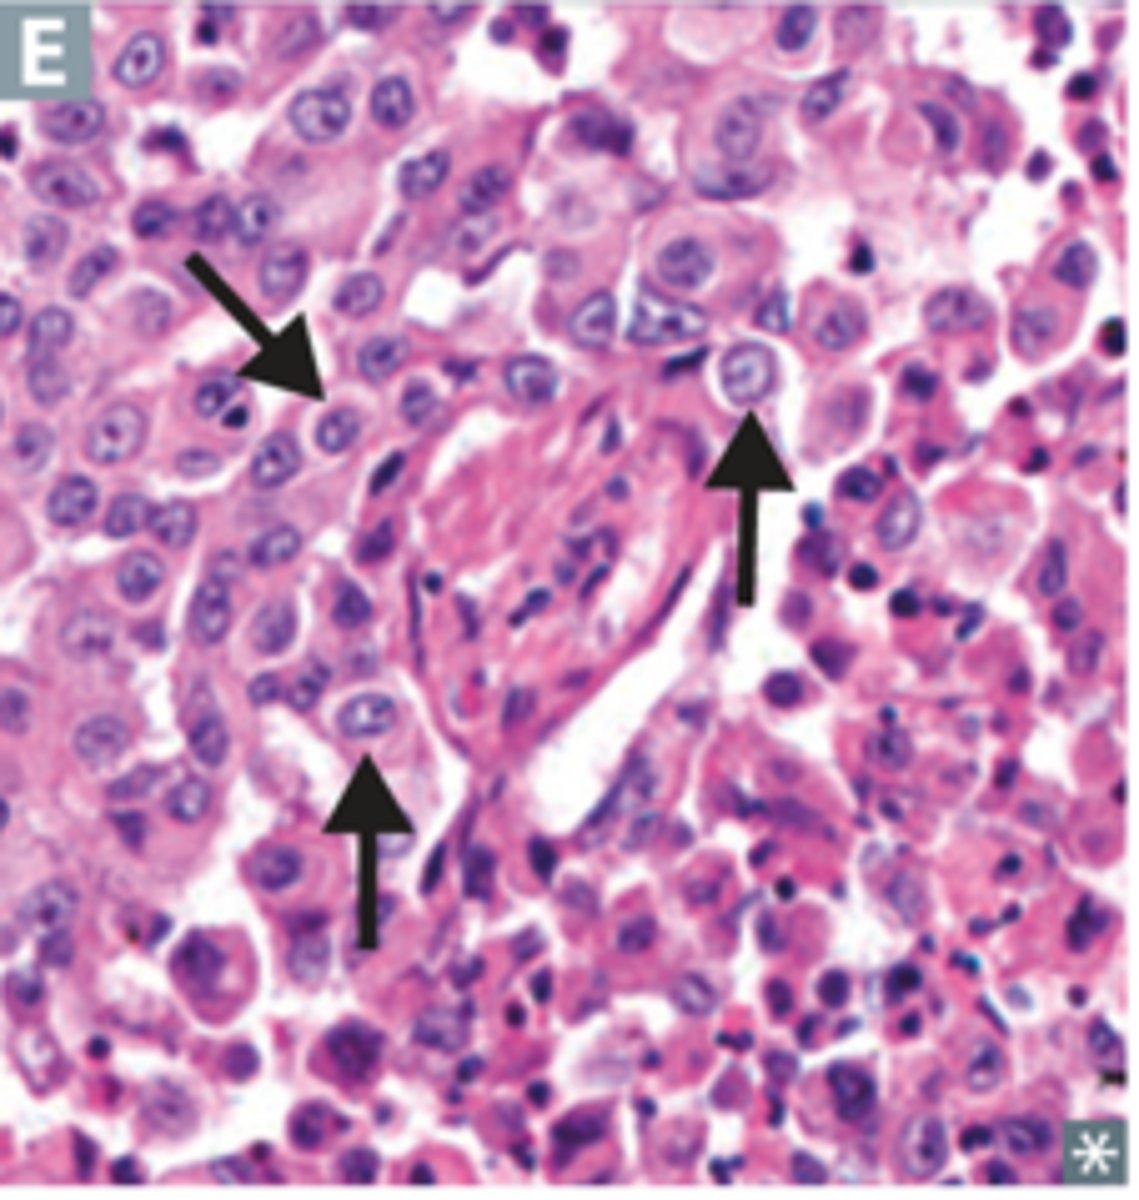

What does a poorly differentiated (Grade III) breast tumour look like?

This is a poorly differentiated (Nottingham Grade 3) breast carcinoma with a combined score of 9 (tubule formation = 3, nuclear pleomorphism = 3, mitotic count = 3)